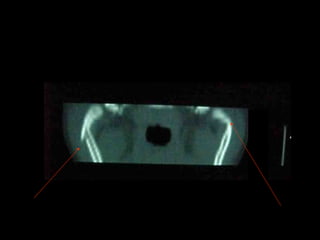

Radiografía

Lateral

De Cara